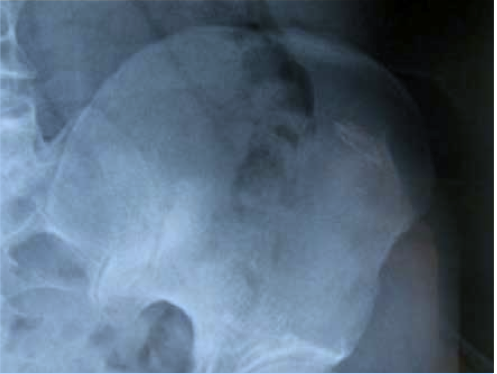

Radiographie à quatre mois : ostéocondensation cicatricielle en dehors de la sacro-ilaque.